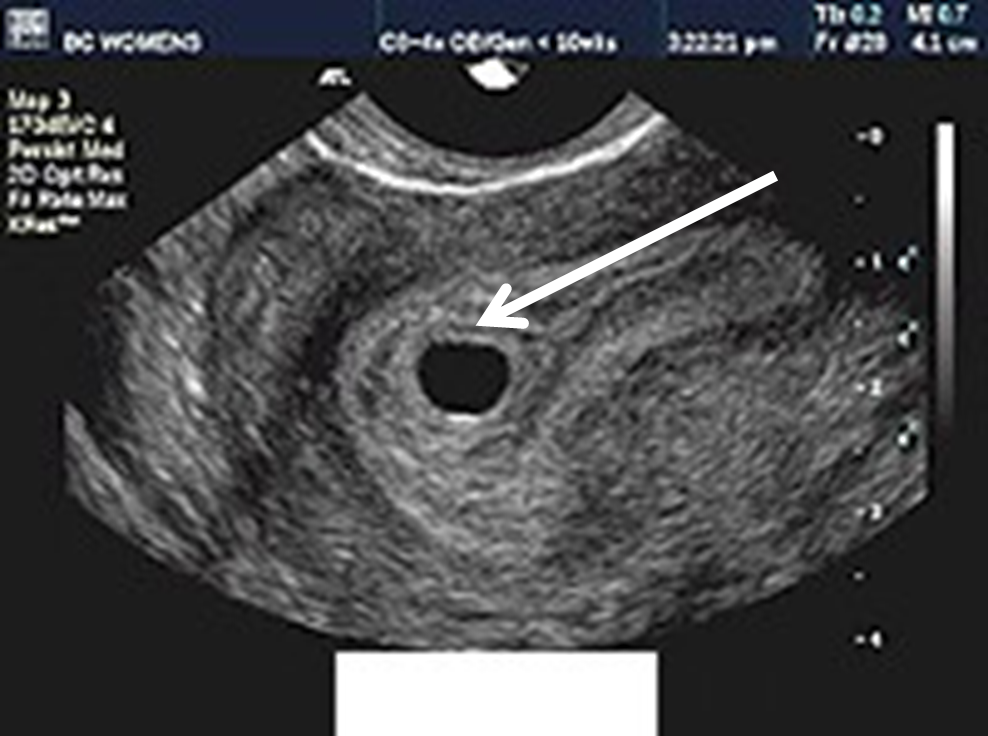

What are the two hyperechoic rings adjacent to gestational sac?

Double Decidual Sac Sign

Typically seen around 7 weeks